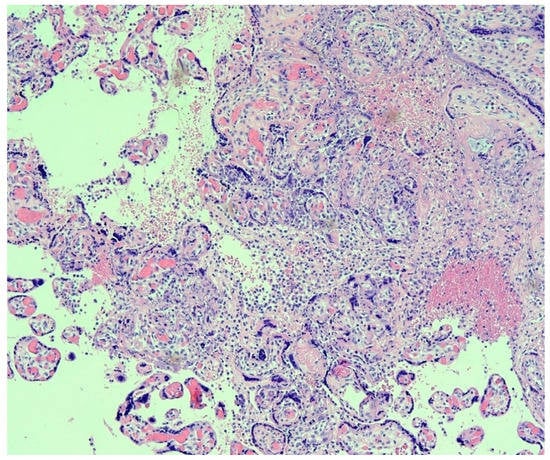

3. Placental Pathology with Evidence of Intrauterine Transplacental Maternal-Fetal COVID-19 Transmission

4. Placental Pathology with Intrauterine Fetal Demise from Mothers with COVID-19

5. Trophoblast Necrosis Together with Chronic Histiocytic Intervillositis Appears to Be a Risk Factor for Placental Infection and Maternal-Fetal Transmission of COVID-19